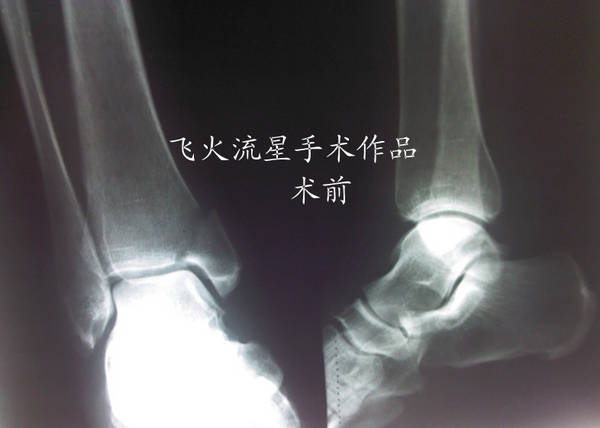

[其他] 内外踝骨折

腓骨下面的三颗固定镙钉进入关节了,病人恢复期会影响关节活动的,要更换短的镙钉。

打的钉子很一般,外踝板不够贴的不进,骨折端没解剖复位,应该打个拉力螺钉,而且外踝板远端钉子有点长,感觉内踝固定不稳定,踝穴看的还凑乎。建议石膏固定一周,要不内踝会出问题,个人愚见

这个病例的胫腓前联合韧带受损应不严重,外踝骨折在联合下!!个人愚见!!